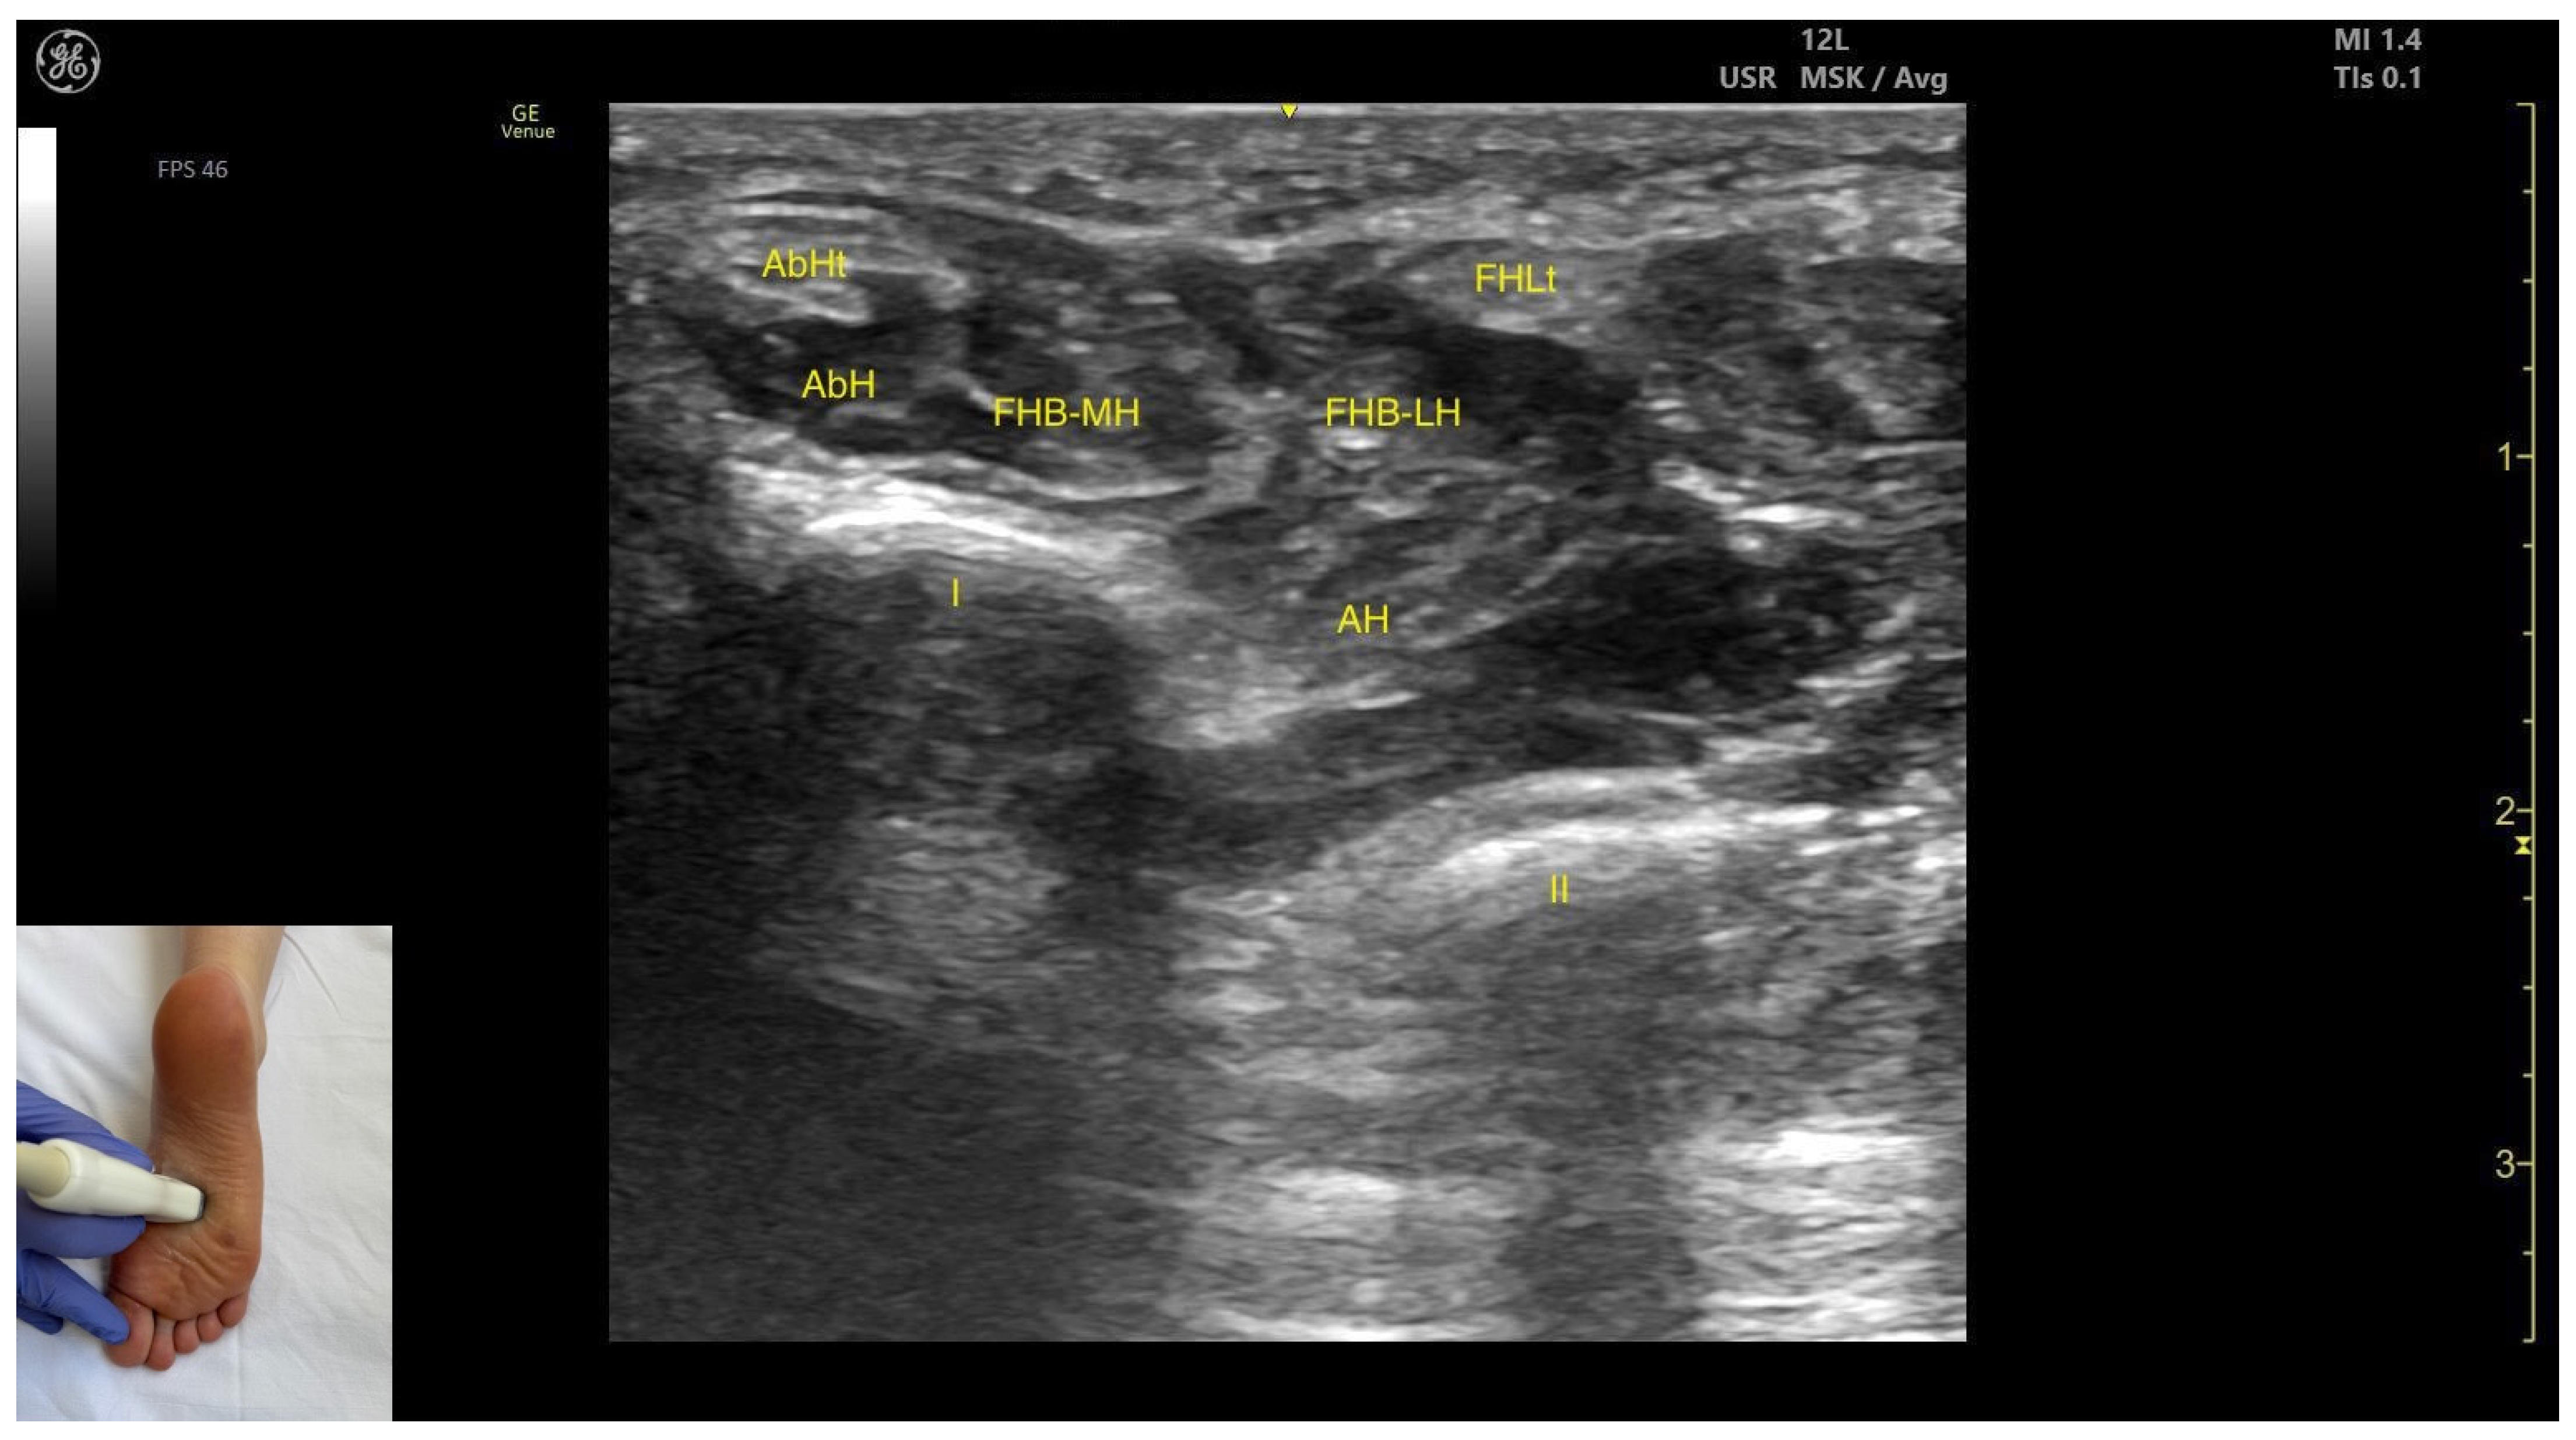

3.9. Flexor Hallucis Brevis (FHB)

3.9.2. Ultrasound Identification

3.9.3. Key Ultrasound Landmarks

- Muscle position: It appears as a superficial muscle mass at this level. Medially, the abductor hallucis muscle and tendon are present; laterally, the tendon of the flexor hallucis longus is visible. Deep and medial to the FHB lies the adductor hallucis.

- Muscle morphology: It has two heads—medial and lateral—that can be targeted individually during BonT-A injection.

- External fascia: FHB has a pronounced fascia that separates it from the superficial tissue, the abductor hallucis muscle, and the tendon of the flexor hallucis longus, during BoNT-A injection.

- Dynamic evaluation: During dynamic evaluation, scanning distally toward the first metatarsophalangeal joint, a decrease in muscle thickness of the flexor hallucis brevis is observed along with its insertion on the medial and lateral sides of the proximal phalanx of the hallux. Muscle contraction is visible during dynamic evaluation when performing hallux flexion at the first metatarsophalangeal joint.

| AH | Adductor hallucis |

| FHB | Flexor hallucis brevis |

| AbH | Abductor hallucis |

| FHB-MH | Flexor hallucis brevis medial head |

| FHB-LH | Flexor hallucis brevis lateral head |

| Flexor Hallucis Brevis | ~1–2 cm proximal to the first metatarsophalangeal joint | Abductor hallucis muscle and tendon (medial); flexor hallucis longus tendon (lateral); adductor hallucis (deep and medial) | Transverse scan ~1–2 cm proximal to the first metatarsophalangeal joint | Visualize flexor hallucis brevis as most superficial muscle and confirm muscle position and relations |